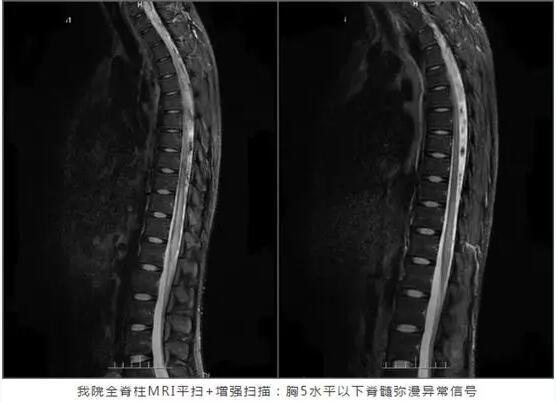

到当地医院就诊后,门诊腰椎MR检查提示“脊髓炎”,而头颅MR则提示无明显异常。在当地医院住院的次日,李凯开始出现小便困难,随后进展为双下肢无力,无法抬起。为寻求进一步的诊治,李凯来到广东三九脑科医院就诊。

出院前复查全脊柱MR平扫+增强,对比入院前影像,胸10至脊髓圆锥病变范围较前缩小,信号强度较前减弱。当前治疗有效,李凯便顺利出院了。